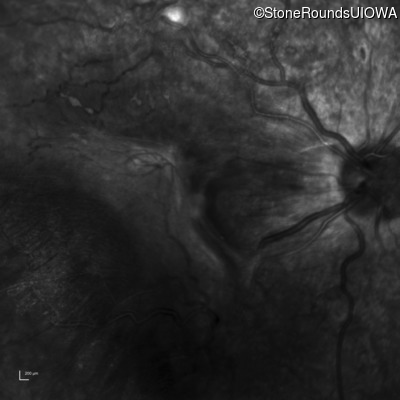

Infrared Fundus Photograph - Left - 20/250 sc

Exemplar